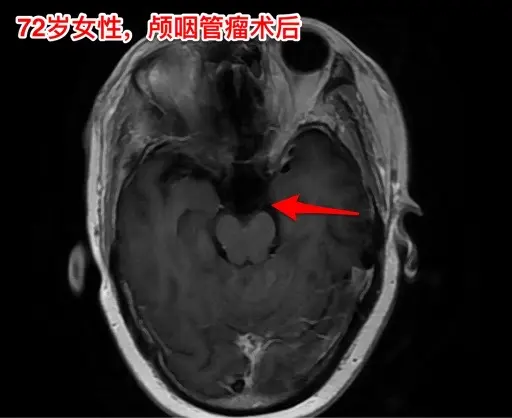

颅咽管瘤不单单是小孩子得的病!很多人认为颅咽管瘤是小孩子得的病,其实各个年龄段的人都可以患颅咽管瘤,我见过的颅咽管瘤病人年龄跨度从不到一岁到八十多岁! 相对而言,小孩子群体中(小于15岁)颅咽管瘤的发生率比较高! 这个72岁的山西晋城市老人在古稀之年患上了颅咽管瘤,病理报告是乳头型颅咽管瘤。10月25日在我科作了手术,11月13日出院。 老人在住院前胃肠功能不好,经常腹胀、消化不良。手术后也是经常感觉腹胀、食欲不振,身体康复过程相对比较缓慢。 老年人一般来说都伴有老年性疾病,比如糖尿病、高血压病、高脂血症、动脉硬化,身体大脏器机能下降,所以老年人患颅咽管瘤,作手术后恢复会比较慢,出意外的风险会增加,尤其是血管方面的并发症会增加,比如深静脉血栓、心肌梗死等。